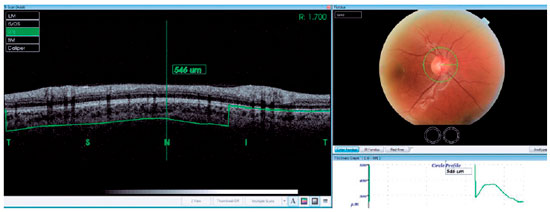

Thirty-four patients who had a history of unilateral evisceration at Sisli Hamidiye Etfal Training and Research Hospital from March 2014 to May 2016 were reviewed retrospectively. Comparative participants who had no ocular diseases were included as controls. High-resolution SD-OCT (3DOCT-2000; Topcon Inc., Tokyo, Japan) was used to evaluate PCT. Thirty-four normal eyes of patients and 34 eyes of healthy controls were subject to a complete ophthalmological examination including medical history, Snellen’s best-corrected visual acuity, slit lamp biomicroscopy, applanation tonometry, and dilated fundoscopy. We selected 3D-OCT circle scan images used to capture retinal nerve fiber layer (RNFL) images in a 3-4-mm zone around the optic disc. The PCT was measured manually and perpendicularly from the outer edge of the hyperreflective retinal pigment epithelium or the Bruch’s membrane opening (BMO) to the choroid-sclera boundary at the nasal, temporal, superior, and inferior quadrants (Figure 1). All SD-OCT measurements were obtained by the same clinician. Exclusion criteria included a diagnosis of open-angle glaucoma, intraocular pressure (IOP) greater than 21 mmHg, presence of other ocular diseases, or previous intraocular surgery. The study was conducted in accordance with the tenets of the Declaration of Helsinki by obtaining written consent from all patients, with the approval of the local ethical review board.

Thirty-four eyes were operated at our Hospital from March 2014 to May 2016. The demographic data and clinical characteristics of the eyes are summarized in table 1. Indications for surgery are shown in table 2. The most common reason of surgery was traumatic phthisis. The age and gender of the subjects were similar (p>0.05). As shown in table 1, the age of the participants in the patient group ranged between five and 84, with a mean age of 40.5 years. The age of participants in the healthy group ranged between 36 and 57, with a mean age of 43. Among the 34 patients, 26 (76.4%) were male and eight (23.5%) were female. The PCT values in the contralateral eyes in the temporal, superior, nasal, and inferior quadrants were 324.0 ± 40.8 µm, 335.8 ± 46.1 µm, 322.7 ± 38.7 µm, and 301.4 ± 46.3 µm, respectively. Furthermore, the PCT values in normal eyes in the four quadrants were 224.7 ± 39 µm, 210.2 ± 36.2 µm, 205.2 ± 35.5 µm, and 199.0 ± 33.1 µm, respectively.

Thus, the PCT values in the contralateral eyes were significantly higher than those in the normal eyes at all quadrants, as shown in figure 2 and table 3 (p<0.05).